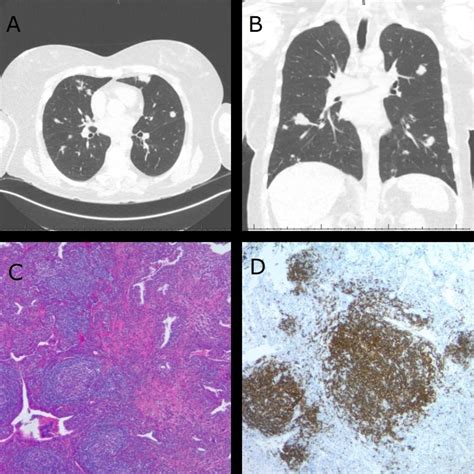

A lung nodule is medically defined as an opacity or a growth that measures less than 3 centimeters in diameter. If the growth is larger than 3 centimeters, it is typically classified as a lung mass, which requires a more urgent investigation. These nodules appear as rounded shadows on imaging scans and can be found in any part of the lungs. It is crucial to remember that finding a nodule does not automatically equate to a cancer diagnosis; in fact, the vast majority of lung nodules identified in clinical practice are found to be benign, meaning they are non-cancerous.

Radiologists use specific criteria to evaluate the risk profile of a nodule. By examining the shape, border, density, and growth rate, doctors can estimate the probability of malignancy. The following table summarizes how medical professionals categorize these features:

Feature Typically Benign (Low Risk) Typically Malignant (High Risk)

Border Smooth, sharp, or clearly defined Spiculated, irregular, or "fuzzy"

Calcification Central, popcorn, or dense Stippled or eccentric

Growth Rate Stable over years Rapid doubling in size

Density Solid, fat-containing Part-solid or ground-glass

• PET Scans: These help determine if the nodule is metabolically active, which can provide clues about whether it is cancerous.

• Biopsy: A sample of the tissue is collected, often through a needle aspiration or a bronchoscopy, to be examined in a laboratory.